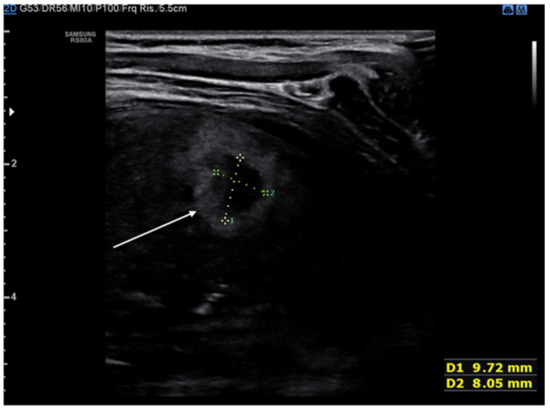

The typical ultrasonographic appearance of CPAM is not yet well defined or univocal, but a large hypoechogenic cystic single lesion, small communicating cystic lesions and consolidations similar to those observed in other lung diseases have been described in several patients (Figure 6). The first two findings, however, appear to be detectable only in this disease [29]. To date, the gold standard for the postnatal diagnosis of these malformations remains the CT of the chest, but ultrasound may in the future represent a useful test to confirm an uncertain diagnosis or follow the patient over time.

Figure 6.

Congenital pulmonary airway malformation. Hepatization is targeted by the upper arrows. The lower arrow highlights the wider anechogenic round cystic areas.